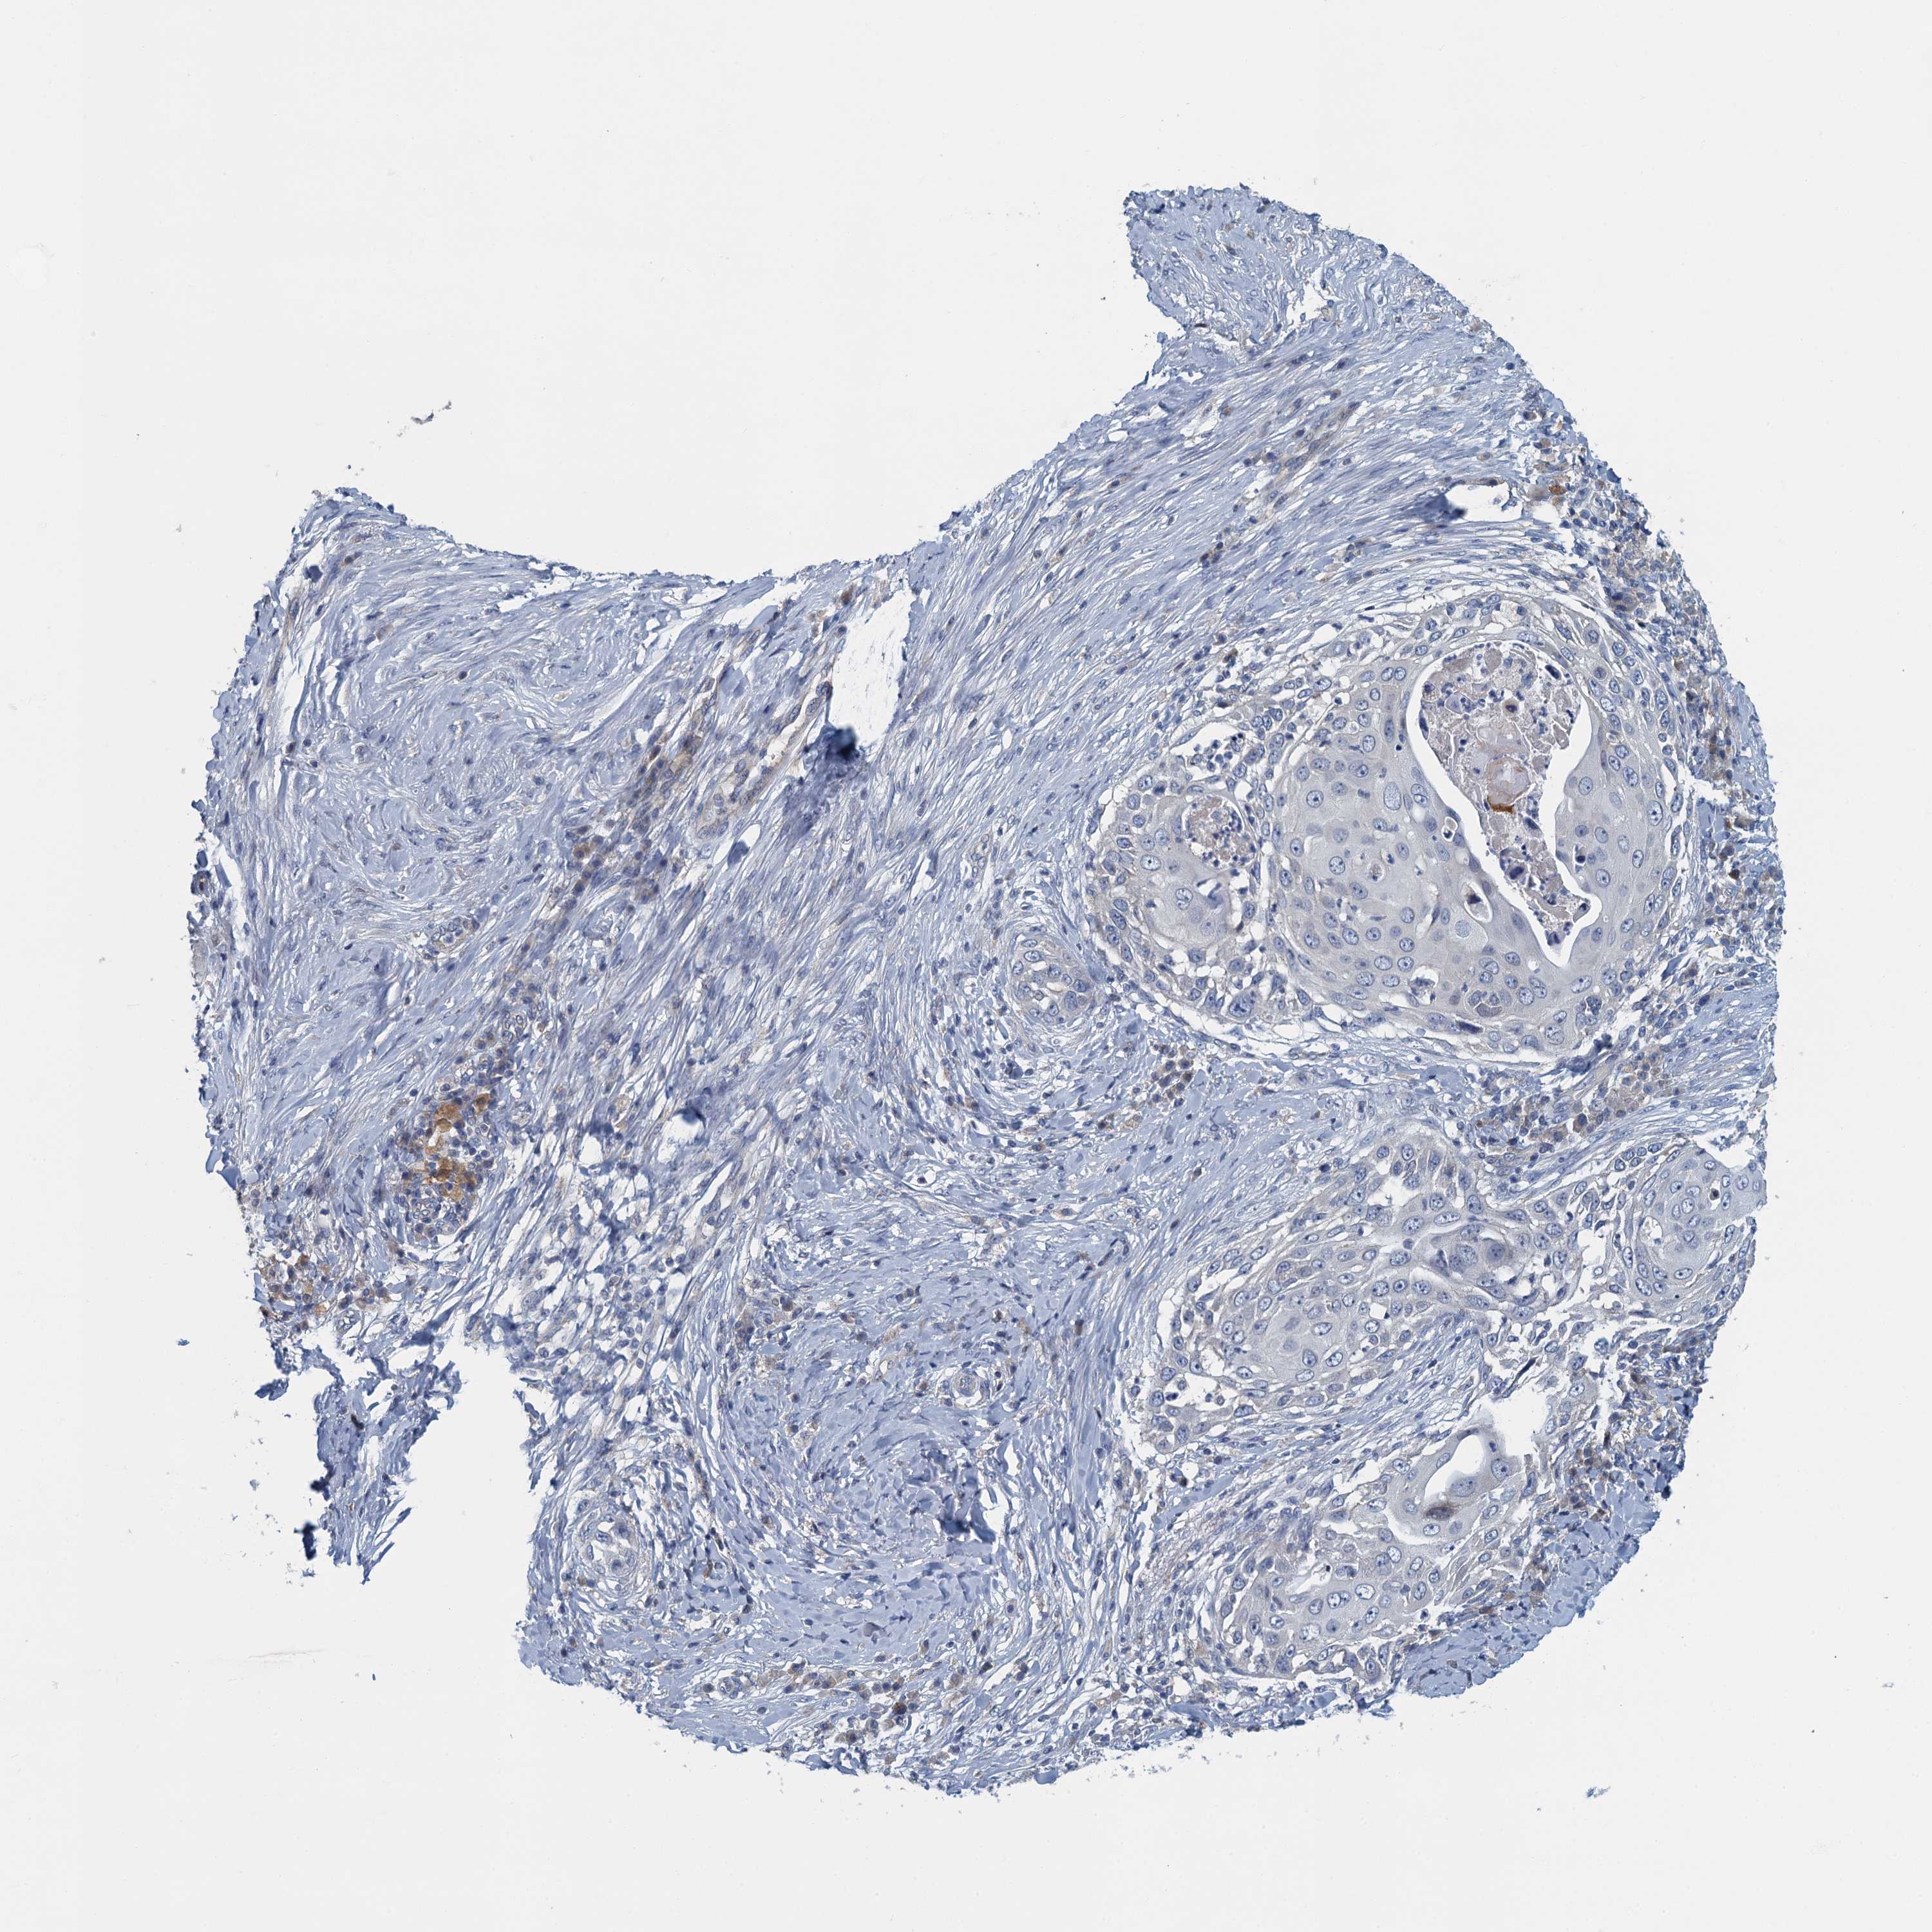

CANCER SKIN CANCER Show tissue menu

Basal cell and squamous cell cancer

SKIN CANCER - Protein expressioni

A mouse-over function shows sample information and annotation data. Click on an image to view it in a full screen mode. Samples can be filtered based on level of antibody staining by selecting one or several of the following categories: high, medium, low and not detected. The assay and annotation is described here.

Each image is clickable and will lead to virtual microscopy that enables deeper exploration of all samples and also displays staining intensity scores, fraction scores and subcellular localization as well as patient and tissue information for each sample.

Antibody HPA039490

Basal cell carcinoma

Squamous cell carcinoma, NOS

Squamous cell carcinoma, metastatic, NOS